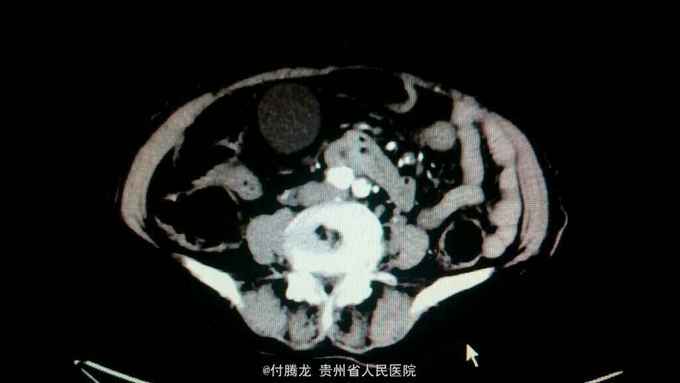

全身黄染伴乏力2月 病史:患者2月前无明显诱因下出现乏力,无恶心呕吐,畏寒发热等,后逐渐发现全身皮肤黄染。遂至当地医院检查。腹部ct提示胆总管下段狭窄,不排除炎性狭窄。胆红素200+。为进一步治疗来我院。

查体:全身皮肤及巩膜重度黄染,上腹轻压痛。 辅助检查:胆红素234,直接胆红素106,间接胆红素128。ALT60,AST88。肿瘤指标199及AFP正常。腹部ct提示胆总管肠内段高密度结节,不排除结石。超声內镜提示胆总管下段梗阻,考虑壶腹部肿瘤。MRCP提示十二指肠壁内段梗阻。